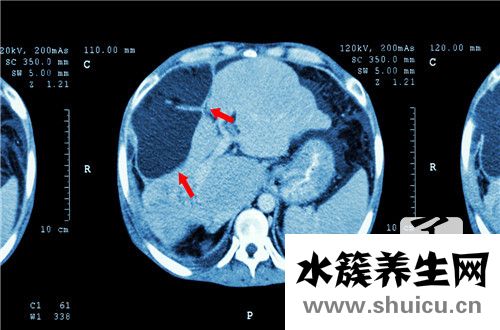

至于以上三種情況應(yīng)該分別怎么去對(duì)待?至于是不是已經(jīng)處于恢復(fù)階段,還要結(jié)合乙肝病毒HBV-DNA進(jìn)行綜合分析,如果說(shuō)乙肝病毒HBV-DNA陰性,則說(shuō)明病情正處于恢復(fù)階段,乙肝表面抗原弱陽(yáng)性通常會(huì)在半年之內(nèi)消失。倘若乙肝病毒HBV-DNA陽(yáng)性,則說(shuō)明病毒復(fù)制仍然活躍,這種情況則很有可能是乙肝病毒發(fā)生變異所產(chǎn)生的結(jié)果,少數(shù)患者的病情會(huì)逐漸加重,應(yīng)加以注意,如果詳細(xì)檢查后數(shù)據(jù)沒(méi)什么異常的話(huà),只要按照劑量接種疫苗,增強(qiáng)自身抵抗力就好。不過(guò)發(fā)現(xiàn)乙肝表面抗原弱陽(yáng)性,要及時(shí)到醫(yī)院進(jìn)行檢查采取治療。